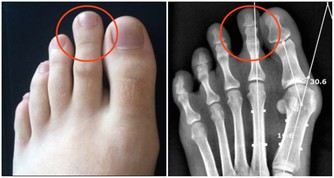

■腿部衰老的8大預警信號

6、雙腿腫脹。

7、 靜脈曲張,腿部血管非常清晰。

8、髖膝關節疼痛,甚至有摩擦磨損、卡住動不了的感覺。